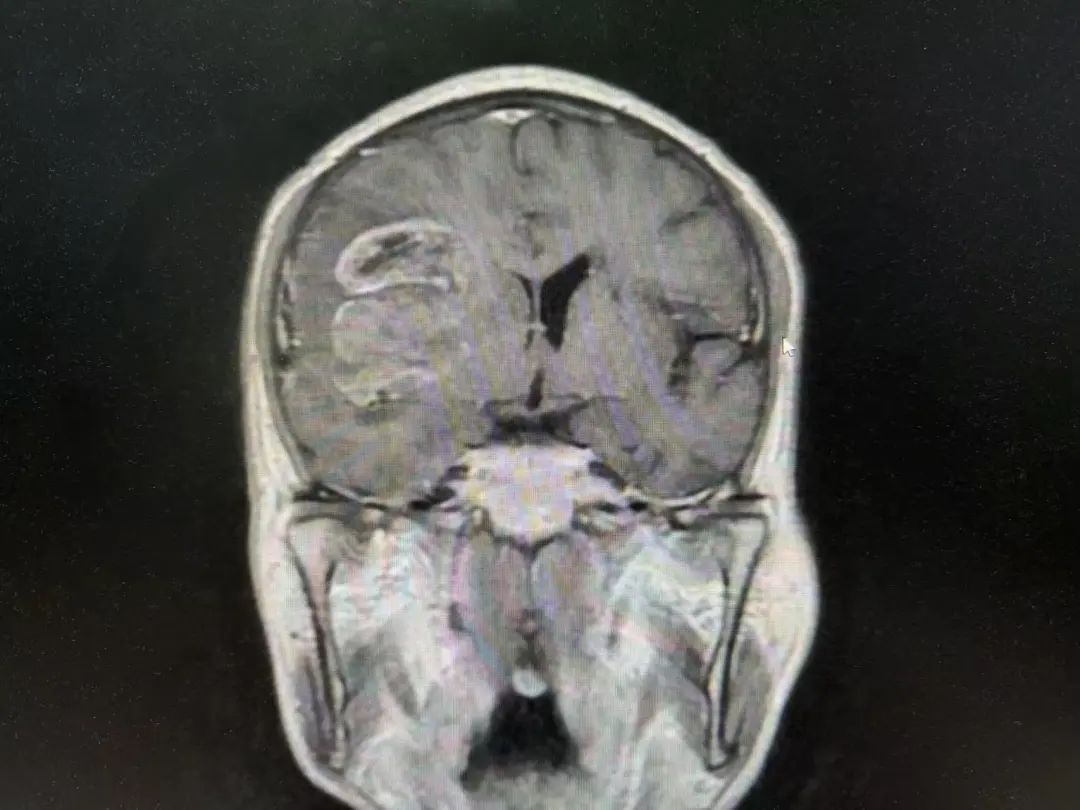

病例特點(diǎn)

男性 | 67歲

主訴:左側(cè)口角流涎10天,左側(cè)肢體無(wú)力7天。

MR:右側(cè)大腦半球腫瘤性病變,考慮高級(jí)別膠質(zhì)瘤(大者大小約3.8cmx4.6cmx3.4cm)。